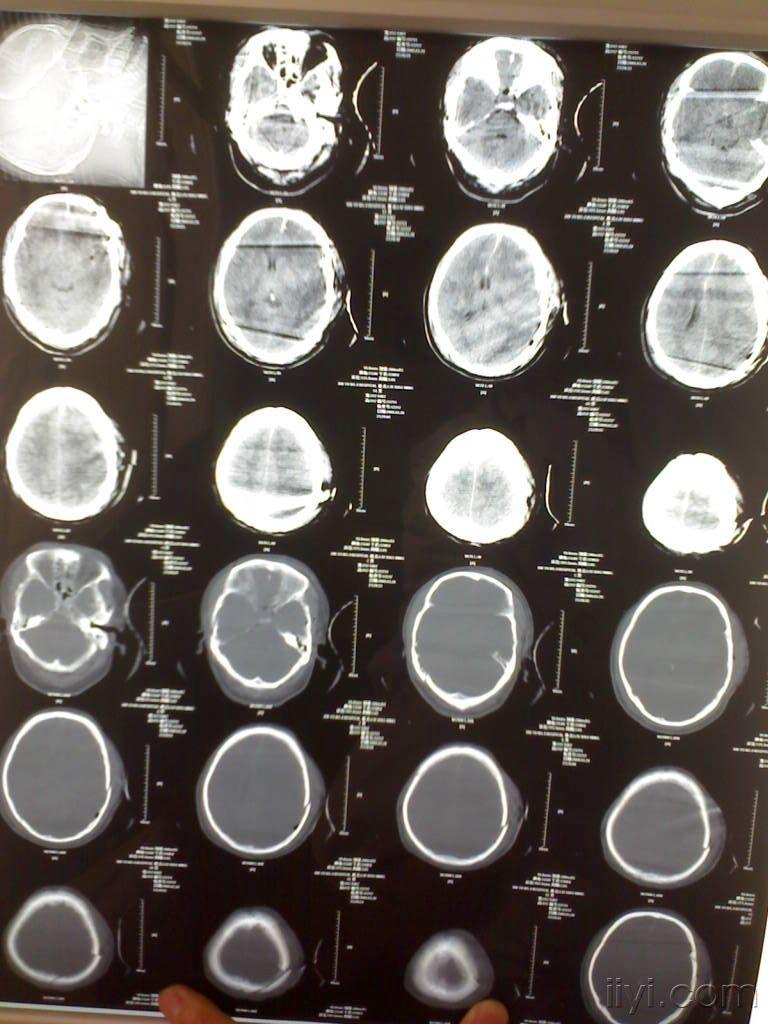

病例1术前ct:侧脑室受压,中线移位

图片尺寸1200x1600